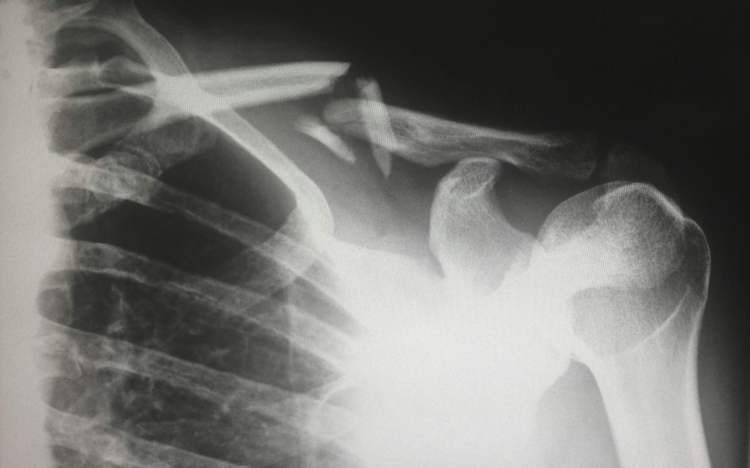

Một người phụ nữ 48 tuổi tại Thành Đô, Trung Quốc đã gây xôn xao dư luận sau khi được chẩn đoán bị gãy xương chỉ vì... xoay người trên giường. Các bác sĩ xác định nguyên nhân là do thiếu hụt vitamin D nghiêm trọng, xuất phát từ thói quen tránh nắng và sử dụng kem chống nắng quá mức suốt nhiều năm.

Theo thông tin từ Bệnh viện Y học Cổ truyền Tân Đô (XinDu), nữ bệnh nhân này chưa từng mặc áo ngắn tay hay để da tiếp xúc với ánh nắng trong suốt thời gian dài. Mỗi khi ra ngoài, bà đều bôi kem chống nắng và che kín cơ thể để tránh nắng. Kết quả kiểm tra cho thấy mức vitamin D trong máu của bà ở mức cực thấp, dẫn đến tình trạng mất xương nhanh và loãng xương nặng.

Trường hợp hy hữu này được bác sĩ Long Song chia sẻ nhằm cảnh báo cộng đồng về nguy cơ từ việc lạm dụng kem chống nắng và tránh nắng cực đoan. Bác sĩ Jiang Xiaobing, Trưởng khoa Phẫu thuật Cột sống Bệnh viện Đại học Y Quảng Châu, cho biết: "Chúng tôi thường gặp những người mặc kín mít từ đầu đến chân để tránh nắng, nhưng điều này thật sự không tốt cho sức khỏe. Toàn bộ xương trong cơ thể được tái tạo hoàn toàn sau mỗi 10 năm, nhưng từ tuổi 30, chúng ta bắt đầu mất dần khối lượng xương với tốc độ 0,5% đến 1% mỗi năm. Việc thiếu vitamin D, không tiếp xúc ánh nắng và chế độ ăn thiếu canxi sẽ cản trở quá trình hấp thụ canxi và làm tăng nguy cơ loãng xương."

Theo các chuyên gia, ánh nắng mặt trời đóng vai trò quan trọng trong việc giúp cơ thể tổng hợp vitamin D, yếu tố then chốt để duy trì sức khỏe xương khớp. Việc tránh nắng hoàn toàn trong thời gian dài không chỉ làm suy yếu miễn dịch mà còn ảnh hưởng nghiêm trọng đến sức khỏe xương.